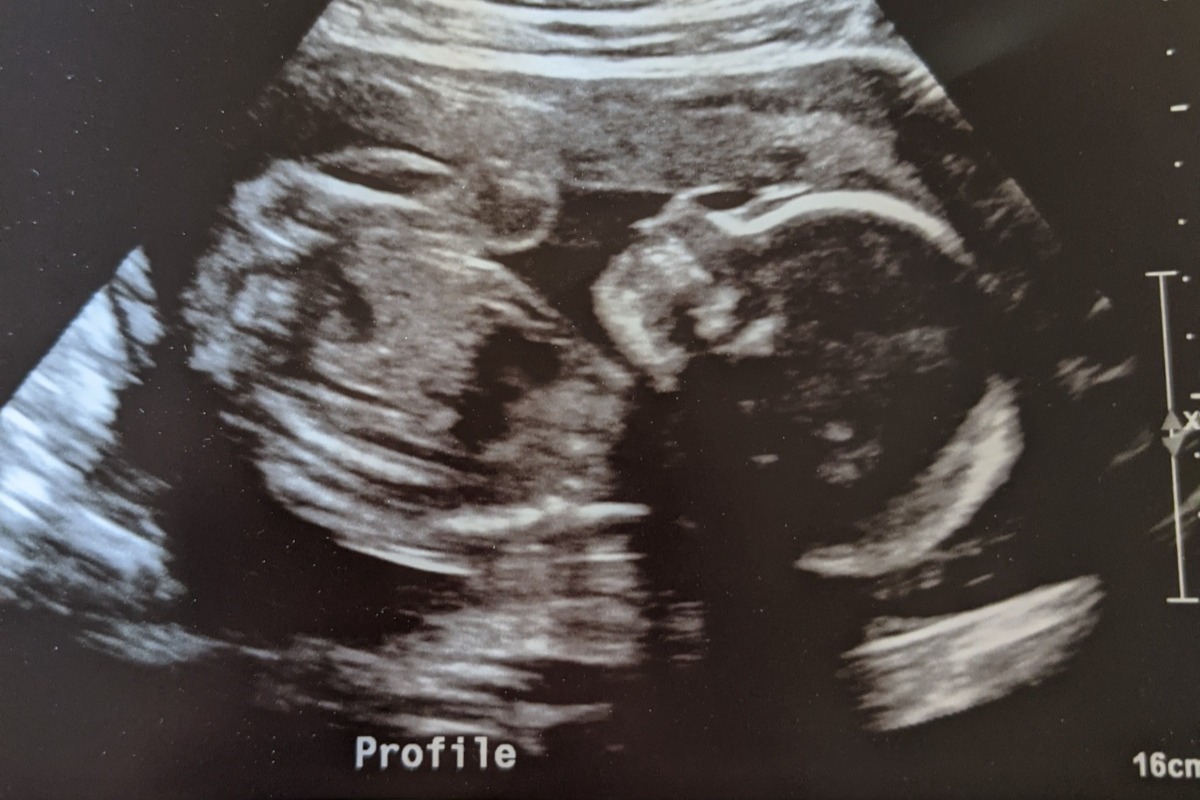

Nicole was going to start a new job but COVID changed everything. She recently started a job within the last couple of months but will not be receiving any sort of maternity leave pay. To add onto the financial stress Nicole & Jake had an appointment to find out what the gender of their baby was going to be. Instead of finding out the gender, they found out their precious baby has a mass on their lower back. They were sent to Boston Children's and Brigham Woman's to run multiple tests for both her and the baby. They found out that the mass was a sacrococcygeal tertoma which means that the mass is a germ cell tumor which later makes up the reproductive system in both men & woman. This specific mass is extremely uncommon and is only seen in one and every 35,000-40,000 babies a year! Nicole will need to have tests run until her scheduled c-section to keep an eye on how fast the tumor is growing, currently its just a little bigger then an orange. The baby will need to undergo surgery within 24 hours of birth to have the tumor and her tailbone removed. I will continue to post updates throughout the rest of Nicoles pregnancy. I completely understand if you can't afford to donate any money but I will gladly take baby clothes (gently used) , diapers/ wipes (sensitive), gas cards to help with getting back and forth to boston, gift cards etc. to help Nicole and Jake get through this time with just a little less stress.